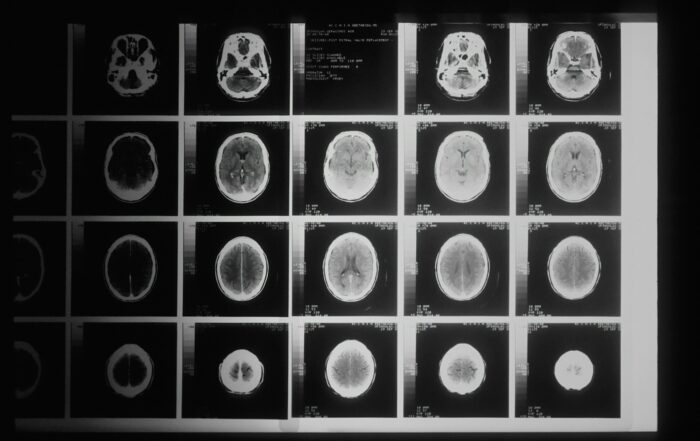

Frontotemporal Dementia (FTD)

A group of disorders characterized by progressive damage to the brain’s frontal and temporal lobes. It can affect people who are quite young — even in their 20s. The loss of nerve cells in these lobes cause deterioration in behavior, personality, and/or difficulty with producing or comprehending language.